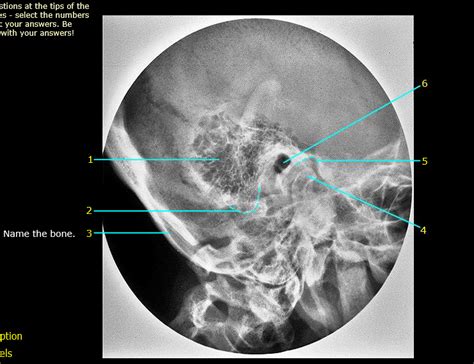

Let’s get down to the nitty-gritty, guys, and talk about the anatomy of mastoid air cells . These aren’t just single, big blobs of air; they’re actually a whole network of interconnected cavities. Think of it like a honeycomb inside the mastoid bone. This process, the mastoid process, is that pointy part of the temporal bone that sticks out just below your ear. Inside this process, you’ve got these spaces, called cells, that are lined with the same kind of mucous membrane that lines your middle ear. The size and number of these cells can vary a ton from person to person. Some people have really extensive, large air cells, while others have fewer, smaller ones. This variation is totally normal and is often determined by genetics. The pneumatization process, which is basically how these air cells develop and fill with air, is super important. It starts in infancy and continues for years. If this process is interrupted or doesn’t happen fully, it can affect how susceptible you are to ear infections. The mastoid air cells are also strategically located. They’re right next to the middle ear cavity, separated by a thin layer of bone. This close relationship is key to understanding why infections can spread so easily. The middle ear is where your eardrum and the tiny little bones that transmit sound are located. When an infection takes hold in the middle ear (think of a nasty bout of otitis media), the inflammation and fluid can easily make its way into the mastoid air cells. This can lead to a cascade of problems. The anatomy is also significant because of what’s nearby. The temporal bone is a real neighborhood of critical structures. You’ve got the auditory ossicles (malleus, incus, and stapes) in the middle ear, the cochlea and semicircular canals of the inner ear responsible for hearing and balance, the facial nerve (which controls muscles in your face), and major blood vessels like the sigmoid sinus. Any inflammation or infection spreading into the mastoid air cells can potentially impinge on or damage these vital components, leading to serious complications like hearing loss, dizziness, or even facial paralysis. Surgeons have to be incredibly careful when operating in this area because of this intricate anatomical arrangement. They need to navigate the air cells while preserving the integrity of the surrounding structures. Understanding this complex network of air cells, their variable nature, and their intimate connection to the middle ear and other critical cranial structures is fundamental to grasping the clinical significance of the mastoid air cells. It’s a testament to the intricate design of the human body, where seemingly simple air pockets play such a vital role in overall ear health and can become a focal point for pathology when things go wrong.